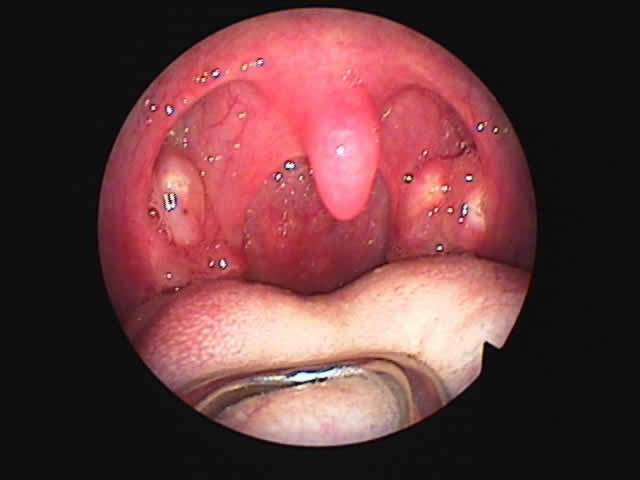

| 左扁桃術直後(31歳男性,6月9日) 数カ所針電極を刺入 | 白い部分が変性部位(6月11日) | 右扁桃術直後(7月7日) |

| 7月16日 かなり縮小 | 両手術直後(縮小不十分なため追加焼灼、8月9日) | 9月8日 著明に縮小しいびき消失しているとのことです |